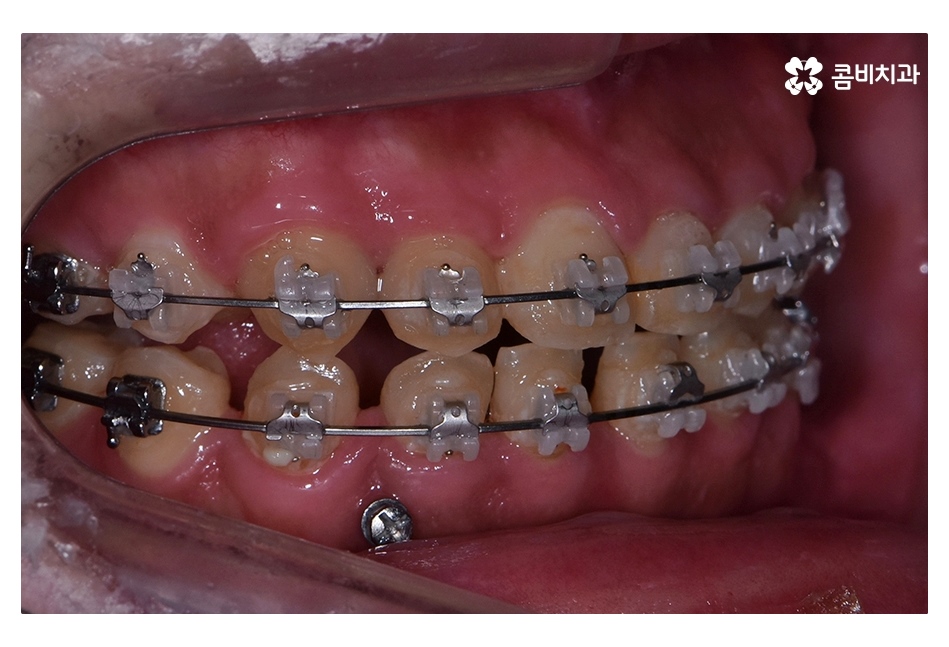

클리피씨교정이 진행되고 시간이 지날수록 아랫니가

점점 윗니에 덮이는 정상 교합의 상태로 개선되는 것을 볼 수 있는데요.

클리피씨교정은 와이어 교체가 간편하며 치아 색과

유사한 세라믹 재질을 사용하기 때문에 심미적으로도 우수한 편이며

일정한 힘을 주어 더욱 빠르게 교정이 가능한 클리피씨교정은

치아교정 환자분들에게 상당히 많이 쓰이고 있는 교정 장치이며

오늘 보신 반대교합의 사례처럼 전체 교정이 필요한 경우에 적합할 수 있어요.